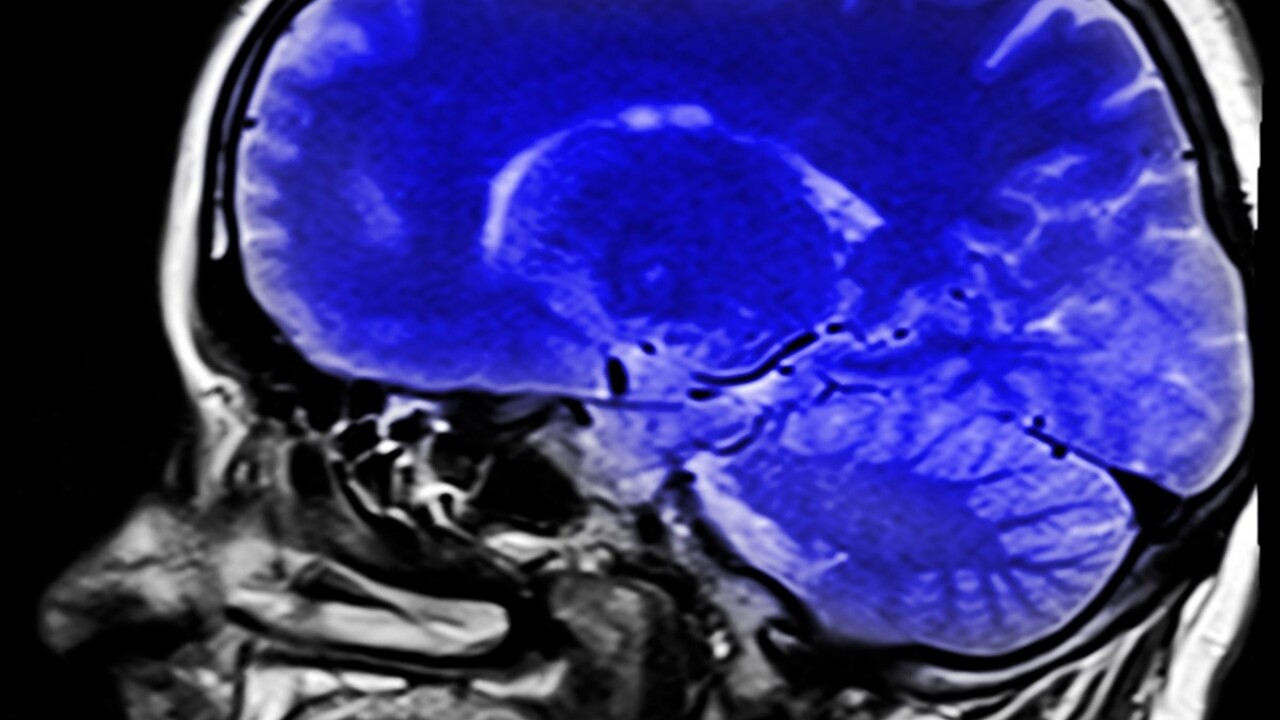

For the correct diagnosis and examination of the disease, an autopsy is performed, reveals a characteristic feature – damage the front and temporal shares of the brain. In the last 25 years, the morphological studies of the dementia of the summit have not been carried out, that is, there was no case of diagnosis about the truth of death.

For the first time in Russia, Perm scientists diagnosed peak disease in a 55 -year -old patient. The woman had no mental disorders, but showed signs of intelligence, aggression, loss of hygiene skills and signs of a progressive decrease in asocial behavior. There were hallucinations in his hospital. A pathological study confirmed characteristic changes in the brain: atrophy of frontal and temporal shares, a body and peak cells.